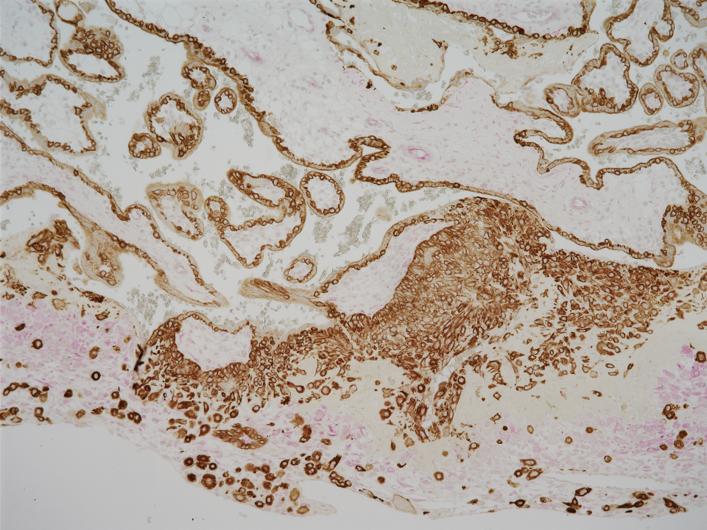

image: In preparation for pregnancy, fetal trophoblast cells (brown) from which the placenta arises invade maternal decidual cells (pink) in the uterus lining.

Image courtesy of Hana Totary-Jain of USF Health, originally published in Scientific Reports: doi.org/10.1038/s41598-020-59812-8

EMT happens early in the formation of the placenta, an organ which attaches to the lining of the uterus during pregnancy and supplies oxygen and nutrients from mother to the growing fetus. During the first trimester, fetal trophoblasts penetrate the maternal uterine lining and modify its blood vessels. This remodeling of the mother's spiral arteries allows oxygenated blood to flow from the mother to fetus.